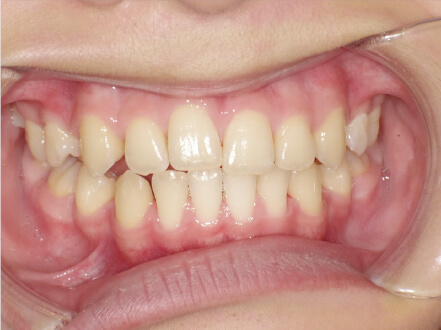

叢生の症例

9歳

/

女性

相談内容

マイオスマイルからの移行

カウンセリング・診断結果

上11捻転、上33スペース不足、インビザで歯列矯正

治療内容・方法

全額アライナー矯正 クリアコレクト

術後の経過・現在の様子

リンガルアーチ使用

治療のリスク

痛み・歯根吸収・歯肉退縮・虫歯・後戻り

費用・治療期間

(マウスピース矯正のみ)440,000円+220,000円 月々27,500円、9ヶ月+myo1年10ヶ